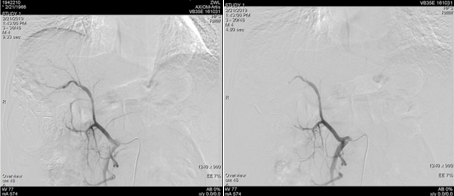

遂继续以碘油4 ml+0.9%氯化钠20 ml+吡柔比星20 mg+雷替曲塞2支方案,行第二次TACE治疗。

图片

图:第二次TACE治疗